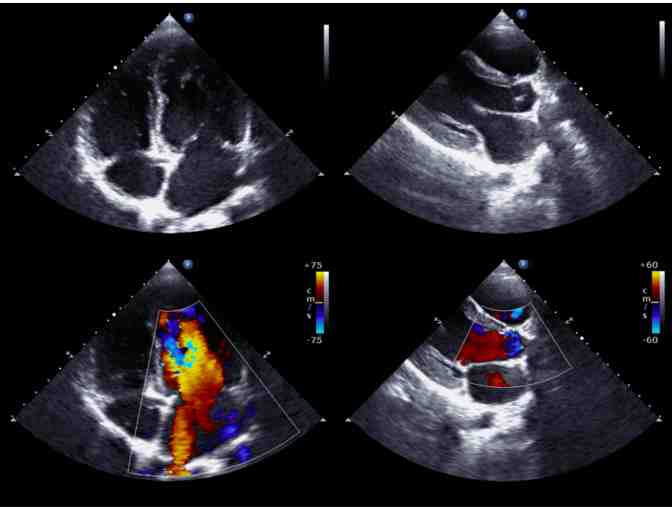

Heart disease is the leading cause of death for men and women in the United States. Stroke is the 5th leading cause of death. Preventive health screenings, which are also non-invasive, can identify risk factors that can lead to cardiovascular disease and stroke. This allows people to understand their risk of developing a condition before symptoms are present so that they can take action. As part of this screening, the individual will receive a limited EKG and a carotid ultrasound to assess plaque buildup.